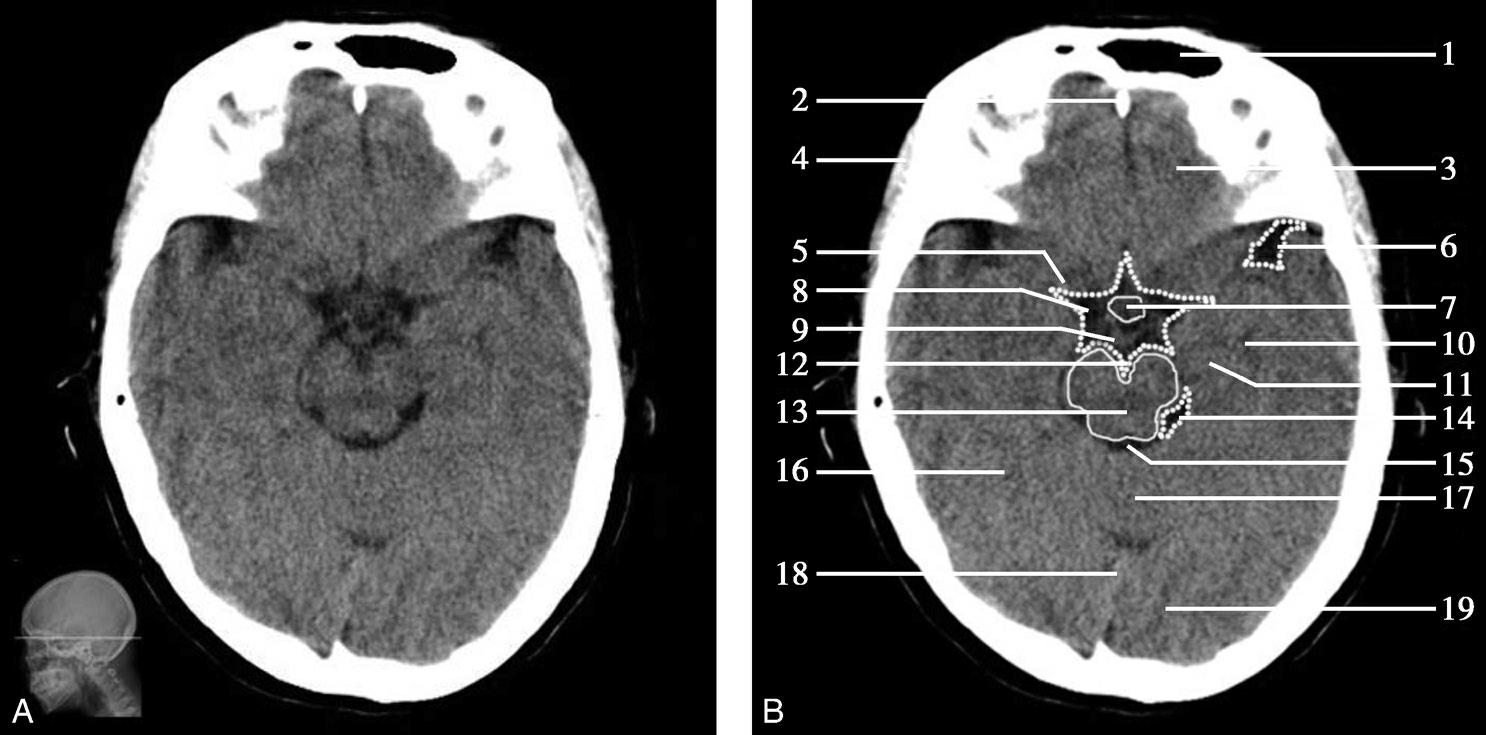

重要结构:卵圆孔、棘孔、破裂孔、斜坡、颞骨岩部、颈静脉孔(图1-2-1、图1-2-2)。

图1-2-1 颅底层面

A.横断面;B.横断面标注

1.晶状体;2.筛窦;3.颞肌;4.中颅窝底;5.外耳道;6.延髓;7.乙状窦;8.小脑半球;9.眼球;10.眼眶;11.上颌窦;12.蝶窦;13.乳突;14.耳郭;15.小脑蚓部;16.枕内隆凸

图1-2-2 颅底层面(骨窗)

1.鼻骨;2.筛窦纸板;3.颧骨眶突;4.翼腭窝;5.蝶骨大翼;6.卵圆孔;7.破裂孔;8.颞骨颧突;9.棘孔;10.斜坡;11.颞骨岩部;12.乳突;13.颈静脉孔;14.枕乳突缝;15.枕骨;16.枕内隆凸

层面前部呈开口向前的“V”字形,正中为鼻中隔,向两侧依次为筛窦和眼眶,眼眶内前部为眼球,后部为眶脂体。翼腭窝位于眼眶后部,窝内含有脂肪并有上颌神经通过。层面中部为蝶骨体,蝶骨体中部可见含气蝶窦,蝶窦后方为枕骨基底部,两者呈前后关系,其上面构成斜坡。蝶窦两侧为蝶骨大翼,其后外侧缘处由前向后可见卵圆孔和棘孔,分别有下颌神经和脑膜中动脉通过。斜坡外侧、岩骨尖前方为破裂孔。蝶骨大翼与眶外侧壁的颧骨借颧弓相连,颧弓和蝶骨大翼之间有咬肌及颞肌。层面中部外侧为外耳道。颞骨岩部呈“八”字形,相互之间借破裂孔软骨、蝶岩软骨结合和岩枕软骨结合连接。岩部后外侧的乳突部内可见乳突小房,乳突部与枕骨相接。岩骨后部可见颈静脉孔,内有颈内静脉、舌咽神经、迷走神经和副神经通过。层面后部为颅后窝,其内可见延髓,延髓前方为延髓前池,内有椎动脉,后外侧为小脑半球下部,后方为第四脑室、小脑扁桃体及小脑蚓部。